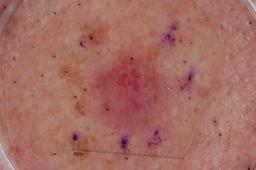

{

"age_approx": 70,

"anatom_site_general": "posterior torso",

"concomitant_biopsy": true,

"dermoscopic_type": "contact non-polarized",

"diagnosis_1": "Benign",

"diagnosis_2": "Benign epidermal proliferations",

"diagnosis_3": "Lichen planus like keratosis",

"diagnosis_confirm_type": "histopathology",

"image_type": "dermoscopic",

"lesion_id": "IL_2099031",

"melanocytic": false,

"sex": "male"

}